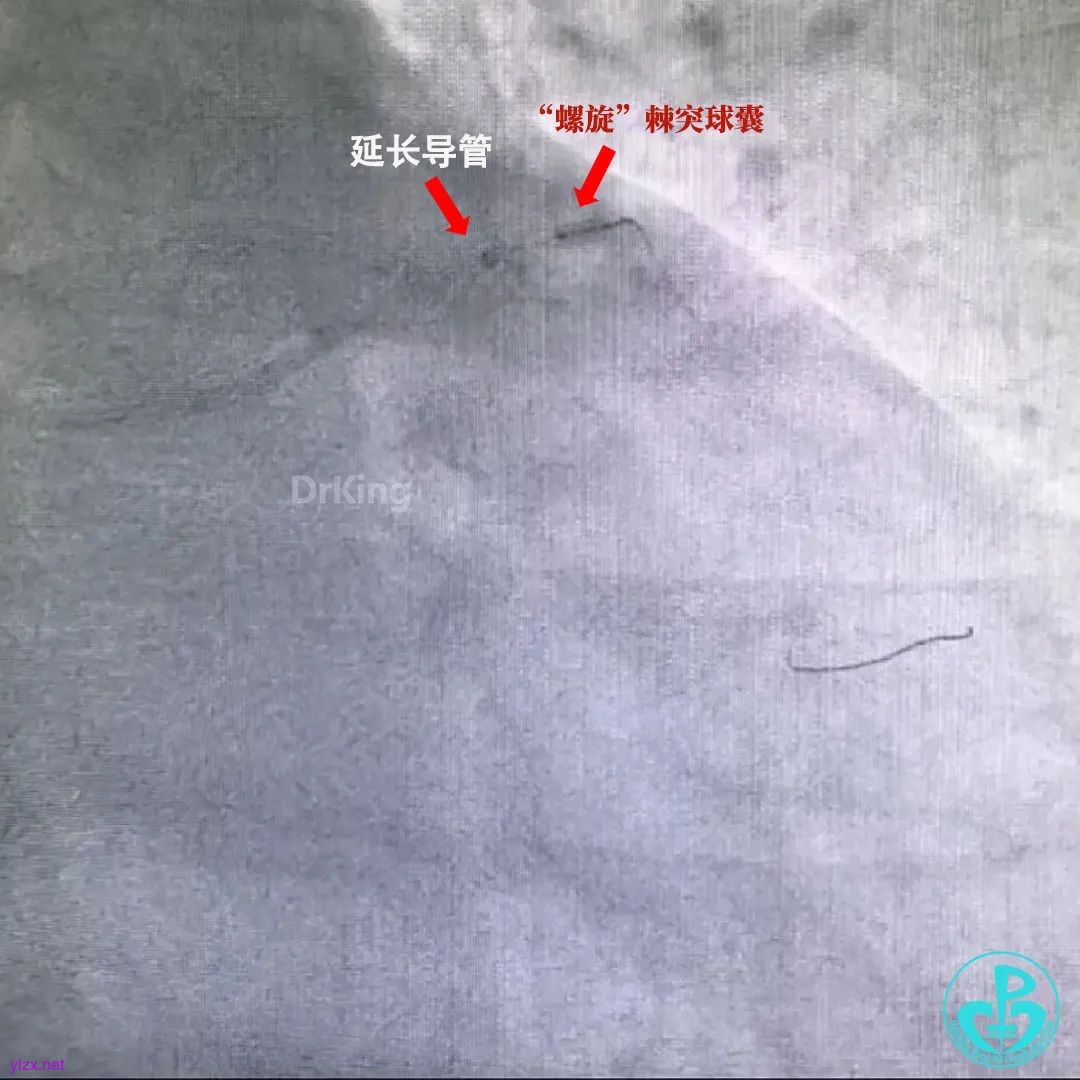

在延长导管和“螺旋”棘突球囊(赛诺医疗)配合下进行拉栓(比Guiding深插安全的多)。

拉栓其实是用导管和“螺旋”棘突球囊把血栓“拘”起来(其他球囊太光滑,起不到向外拖拽血栓的作用),相互配合,这样操作没有血栓掉到主动脉的风险。